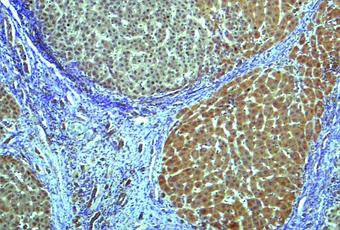

- le test permet même de différencier l’existence d’un parent au premier degré atteint, d’une cirrhose non diagnostiquée avec une précision de 87% ; ces résultats sont ici confirmés par imagerie par résonance magnétique (IRM : voir visuel ci-contre de scanner du foie avec cirrhose).

Source: Nature Communications 29 March 2019 A gut microbiome signature for cirrhosis due to nonalcoholic fatty liver disease (Visuel 2 UC San Diego Health)